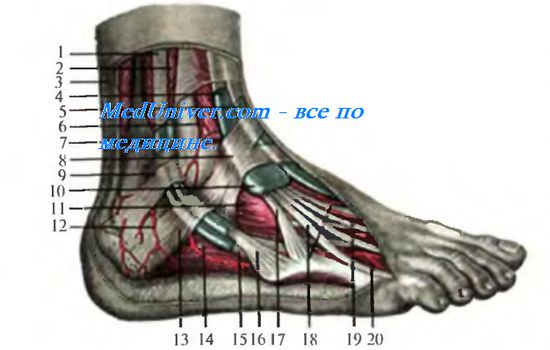

Анатомия голеностопа: Сухожилия и их строение